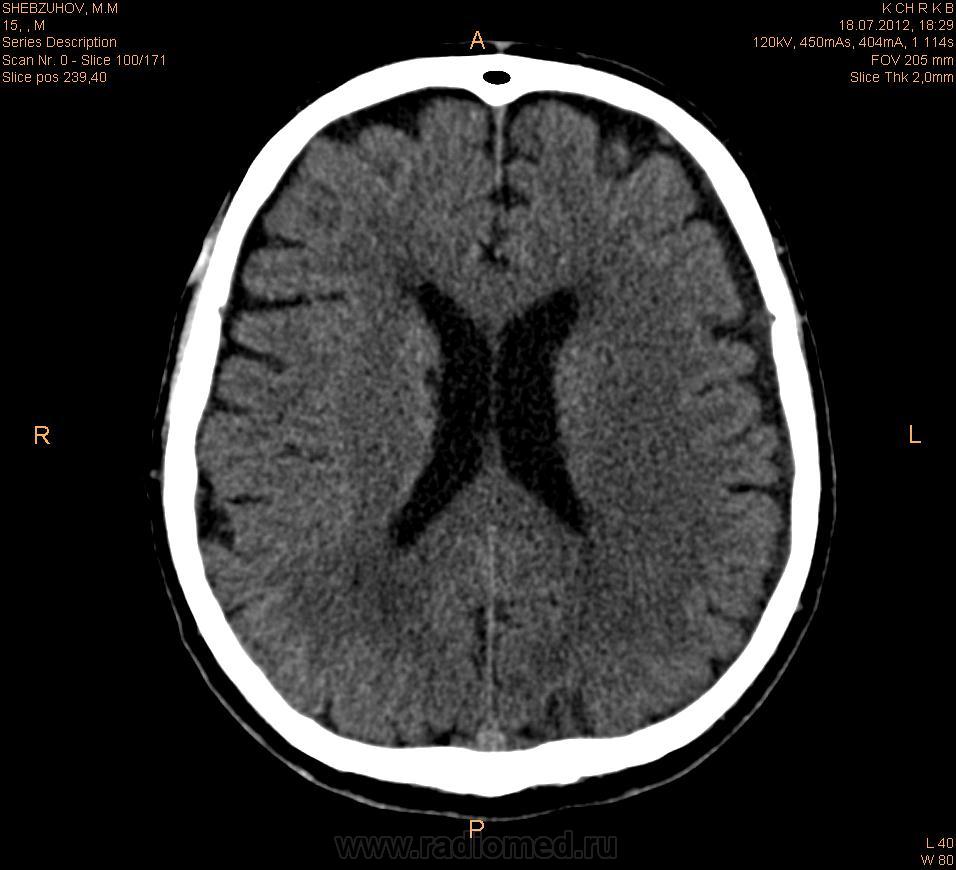

субарахноидальное кровоизлияние?

Субарахноидальное кровоизлияние или это  гиперденсивная связка?

пациент поступил через 7 ч от нач. заболевания . с диагнозом ОНМК по ишемическому типу в бассейне левой СМА.

По мне так - кровушка, а раз спонтанный и нетравматический - даешь ангиографию. У нас такой стандарт по ПСО.

И еще мне не нравится 4й желудочек, не ужто такое сосудистое сплетение? Нет ли крови, или еще чего хуже - образования?

Иногда встречается тромбоз поперечного синуса. Сделайте с контрастом. Изменения при инсультах появляются около 12-16 часов после начала. Повторите исследование, заодно и контраст.

С четвертым желудочком все в порядке. Насчет крови, надо посмотреть коронары, все станет ясно. Вроде синусы, широковаты. А симптоматика кровоизлияния есть?

Контраст -синус тромбоз похоже согласен с коллегами